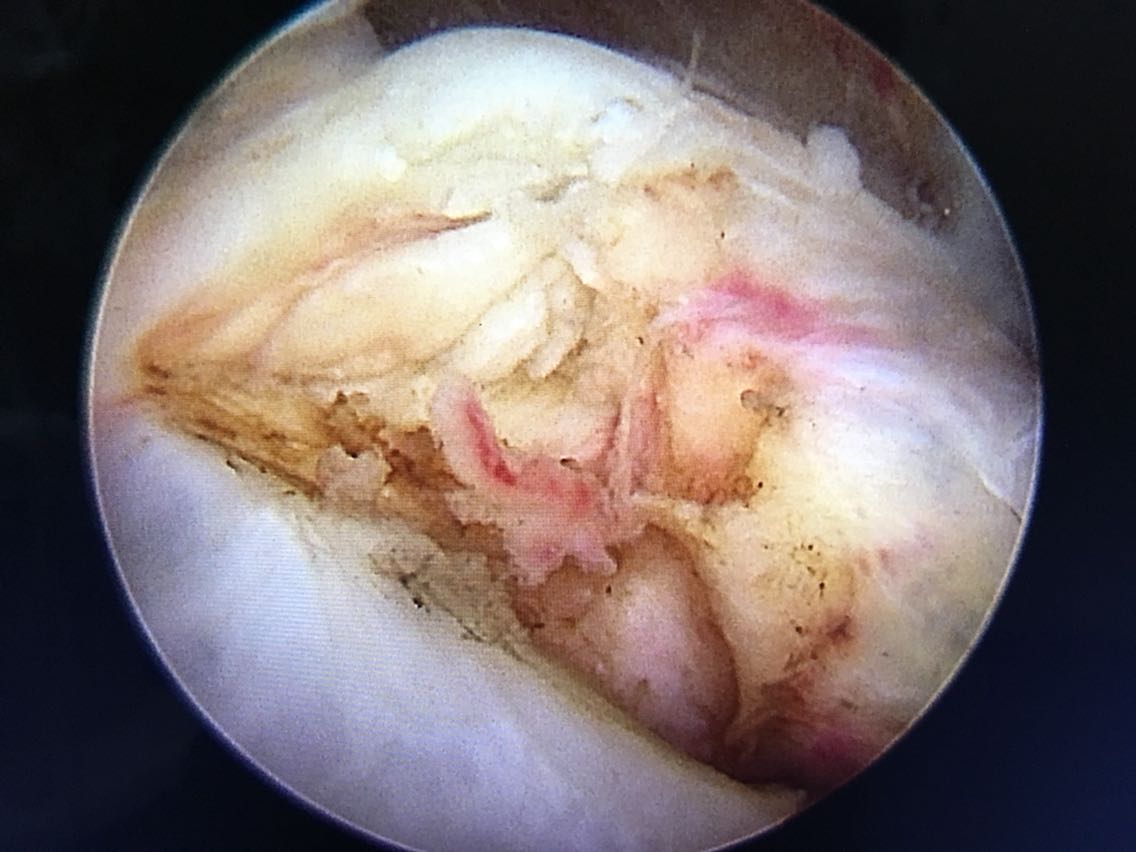

主诉:右肩关节疼痛、功能障碍6个月 现病史:患者于6个月前出现肩关节疼痛,以夜间明显,在当地医院诊断为肩周炎,给予指导关节功能锻炼,疼痛症状和功能障碍加重,效果不佳,来院就诊,核磁共振检查后,诊断为:肩袖撕裂 肩峰撞击症。收入院行关节镜下清理 肩峰成形 肩袖撕裂修补手术。

诊断:右肩袖撕裂 肩峰撞击症 冻结肩 治疗:关节镜下清理 肩峰撞击成形 肩袖撕裂修补手术。